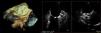

In the procedure, the middle portion of the interatrial septum was punctured (Figure 3) and PMV was performed first by the usual technique with a Mullins sheath and a Brockenbrough needle and inflation of a 26 mm Inoue balloon (Figures 4 and 5), with a good result (absence of transmitral gradient, 2.1 cm2 mitral area and no increase in the degree of valvular regurgitation). Percutaneous LAA closure was then performed. Keeping the guidewire in the same transseptal puncture, a pigtail catheter was introduced into the LAA to allow selective injections into this structure (Figure 6). A 30 mm Amplatzer Cardiac Plug (ACP) (St. Jude Medical), specific for percutaneous LAA closure, was inserted via the ACP release sheath and implanted in the left appendage. It was released successfully and without complications (Figures 7 and 8).